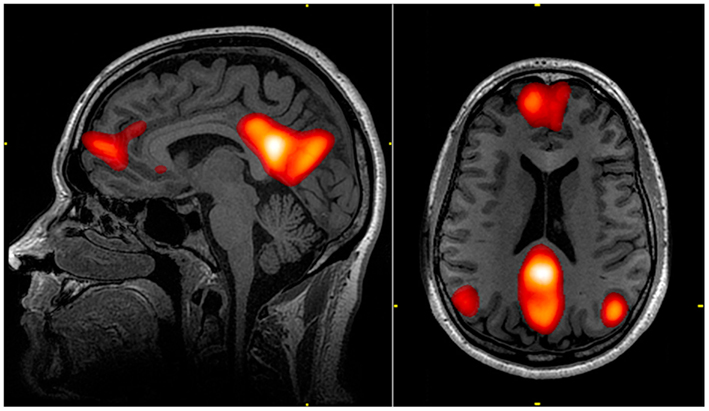

La DMN es una región del cerebro que se activa cuando no estamos concentrados en una tarea específica, es decir, cuando nuestra mente está “en reposo”. En otras palabras, esta red sería como el “piloto automático” del cerebro. Pues, se activa cuando no estamos enfocados en una tarea específica. Pero también, desempeña un papel importante en la regulación de emociones, la toma de decisiones y recuperación de recuerdos. En añadidura, es sensible a los estados emocionales y ritmo circadiano.

Por otro lado, esta red se divide en tres principales subdivisiones (Raichle, 2015):

- Corteza prefrontal ventral media: Relacionada con la recepción de información sensorial del mundo exterior y del cuerpo. La información que recibe la transmite a áreas cerebrales responsables de regular las emociones, comportamiento social y motivación. Asimismo, su actividad está influenciada por el estado emocional de la persona, disminuyendo cuando la ansiedad es alta y aumentando cuando disminuye.

- Corteza prefrontal medial dorsal: A diferencia de la anterior, esta área está más relacionada con la toma de decisiones y juicios sobre uno mismo. Por lo tanto, al realizar tareas que requieren atención y concentración se activa, mientras que la anterior se desactiva.

- Corteza cingulada posterior y precúneo medial: Por último, las siguientes regiones están involucradas en la recuperación de información previamente almacenada en la memoria. Además, muestran una fuerte conexión con el hipocampo, que desempeña un rol relevante en la memoria. Curiosamente, la actividad de esta red varía durante el día, siendo más fuerte por la noche y más débil por la mañana después de una noche de sueño.